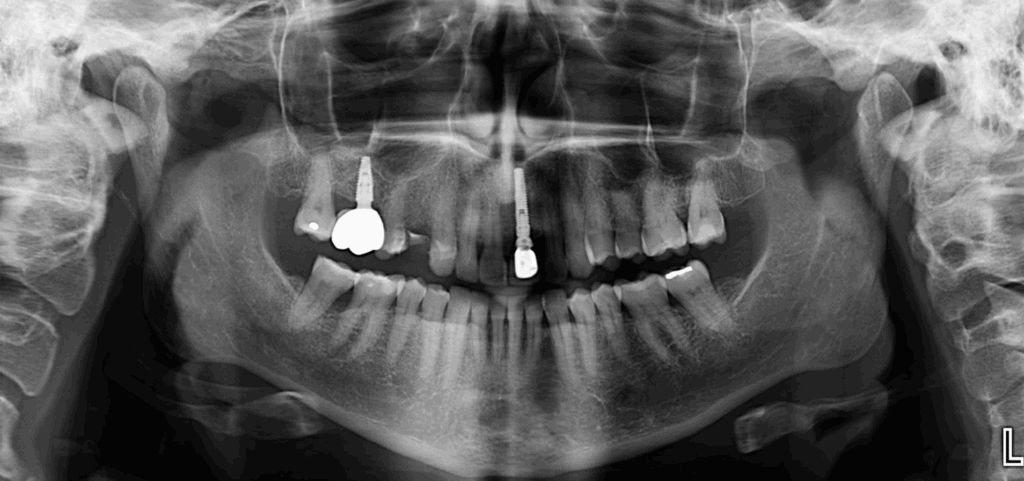

A la evaluación de la tomografía de campo mediano (10 x 10) se observa una imagen hiperdensa que no se evidencia en la radiografía, de forma irregular y limites definidos localizada en tejido blando a nivel de piso de boca y de las piezas 36 y 35 compatible con sialolito submandibular.

CORTES AXIALES